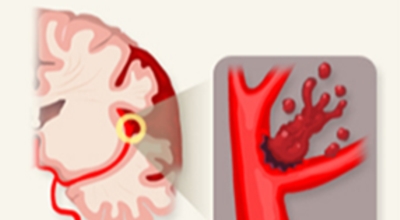

뇌졸중은 뇌경색과 뇌출혈 두가지로 나뉘게 돼요. 먼저 뇌경색은 뇌혈관이 막혀 영양분과 산소를 주는 피가 통하지 않는 상태로 원은은 크게 세 가지로 나눌 수 있는데요 동맥경화증이 생겨 좁아진 부위로 인하여 혈액공급이 부족해지거나 좁아지다가 결국 막혀버리는 경우, 큰 혈관에서 분지한 작은 혈관들이 고혈압 등으로 압박을 받으면 혈관이 막히는 경우가 있습니다.

또한 심장 판막질환이나 심방세동 또는 심근병 등등의 심장 질환이 있는 경우 심장에서 혈전이 만들어지고 그게 뇌로 흘러가게 되면 뇌혈관을 막게 되는 경우가 있답니다. 뇌출혈은 뇌경색과 반대로 뇌혈관이 터져서 생기는 뇌내 출혈과 거미막하 출혈로 나누게 돼요. 거미막하출혈은 혈관벽의 약한 부분이 부풀어 오르는 뇌동맥류가 터지는 경우와 관련성이 크다고 해요.